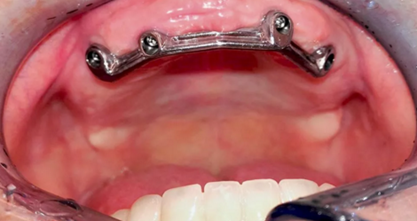

在下次就診時(shí),檢查切削研磨后 Dolder 桿卡的就位,及密合度,防止種植體間的張力,確保新義齒有最佳的適合性(圖 10)。

(圖10)